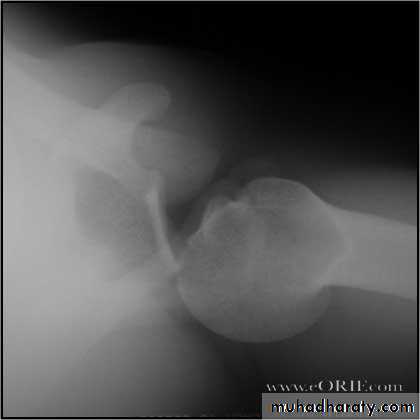

Fall on out stretched hand

xray